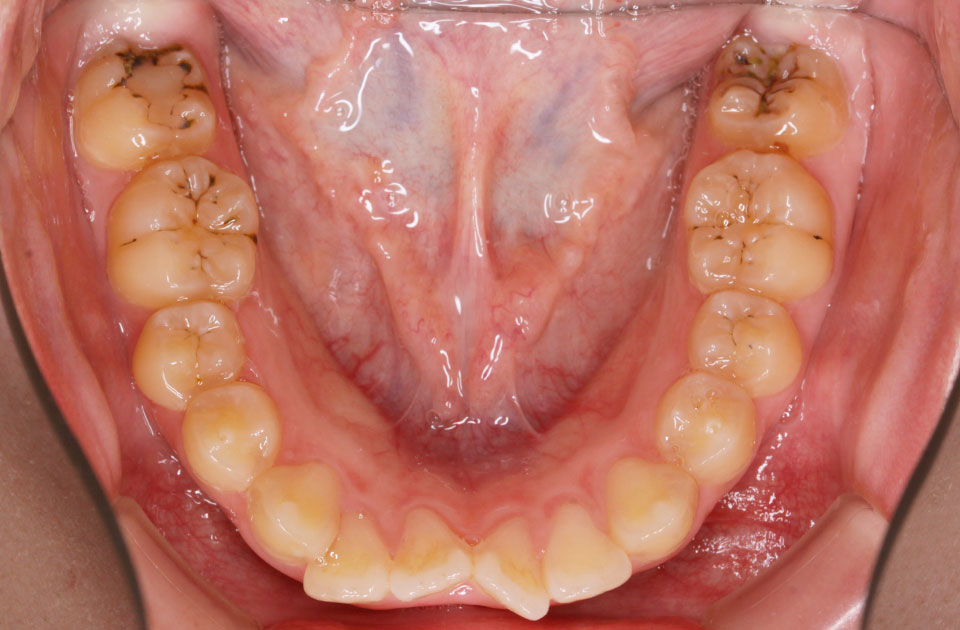

矯正前 下顎